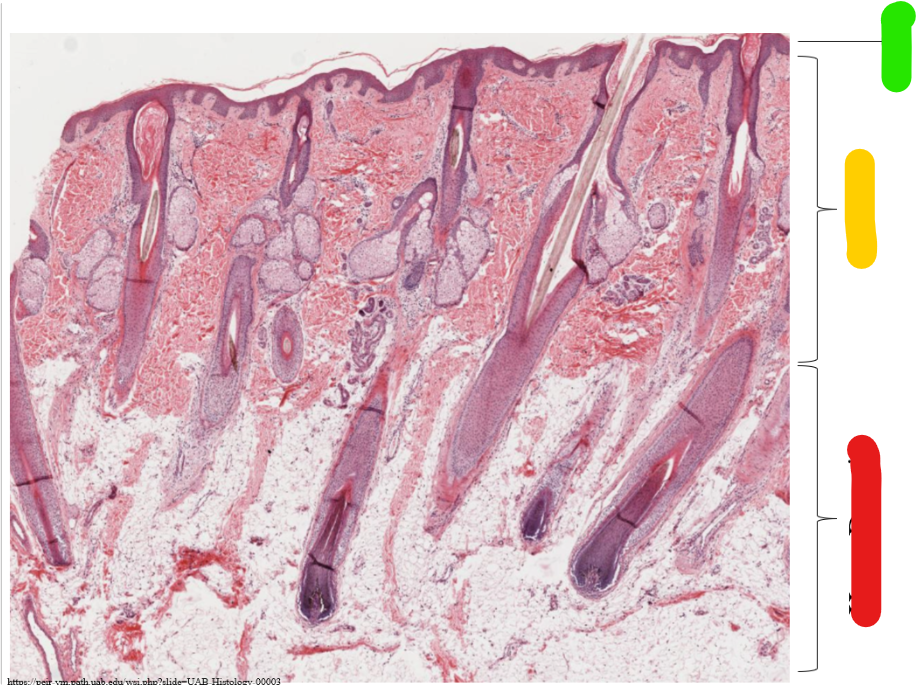

green

epidermis

yellow

dermis

red

hypo dermis